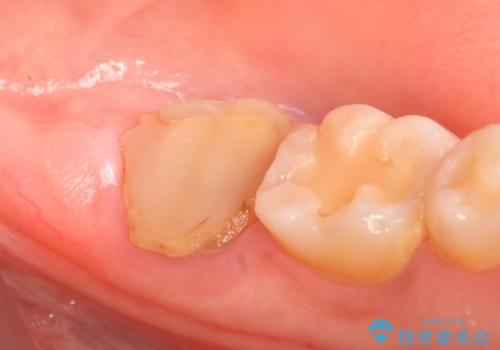

- 左下の一番奥の歯が時折激しく痛むので診て欲しいといらっしゃった方の症例です。以前に他院を受診したところ、そもそも被せ物を入れるスペースがないため抜歯しかないと言われたとのことでした。

診査の結果根尖病変を認めたため再根管治療を行った後に、被せ物を入れるスペースを作るため歯冠延長術を行いました。

歯冠延長術について

歯冠長延長術とは歯肉弁根尖側移動術とも言い、歯の高さが低くクラウン(被せ物)による治療が難しい場合に、歯茎を歯根方向に下げることで歯の高さを確保する手術です。歯の高さが十分にあることで、外れにくいしっかりとしたクラウンを被せることができます。